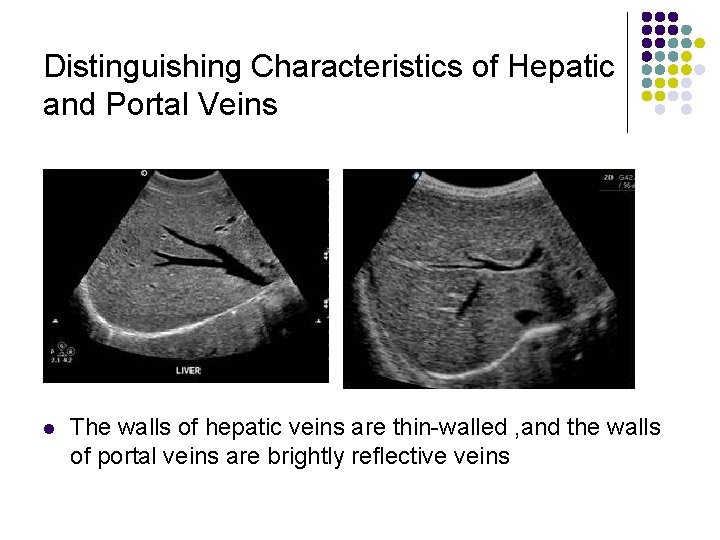

Distinguishing Characteristics of Hepatic and Portal Veins l The walls of hepatic veins are thin-walled , and the walls of portal veins are brightly reflective veins

l l l The hepatic veins are easily differentiated from bile ducts and portal veins. They are not surrounded by an echogenic wall They originate close to the diaphragm , and can be traced into the inferior vena cava